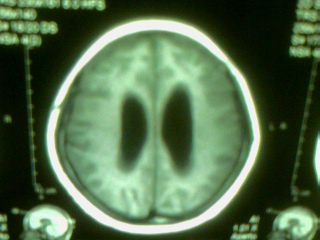

标题: MRI2125:女 45岁 头疼头晕3个月 [打印本页]

标题: MRI2125:女 45岁 头疼头晕3个月

1)考虑第四脑室脉络膜丛乳头状瘤,不排除室管膜瘤。2)阻塞性脑积水。

考虑 第四脑室室管膜瘤或脉络膜丛乳头状瘤伴梗阻性脑积水。

1)考虑第四脑室室管膜瘤,不排除脉络膜丛乳头状瘤。2)阻塞性脑积水。

考虑 第四脑室室管膜瘤或脉络膜丛乳头状瘤伴梗阻性脑积水

考虑 第四脑室脑膜瘤或室管膜瘤或脉络膜丛乳头状瘤伴梗阻性脑积水

第四脑室脉络丛乳头状瘤,典型!